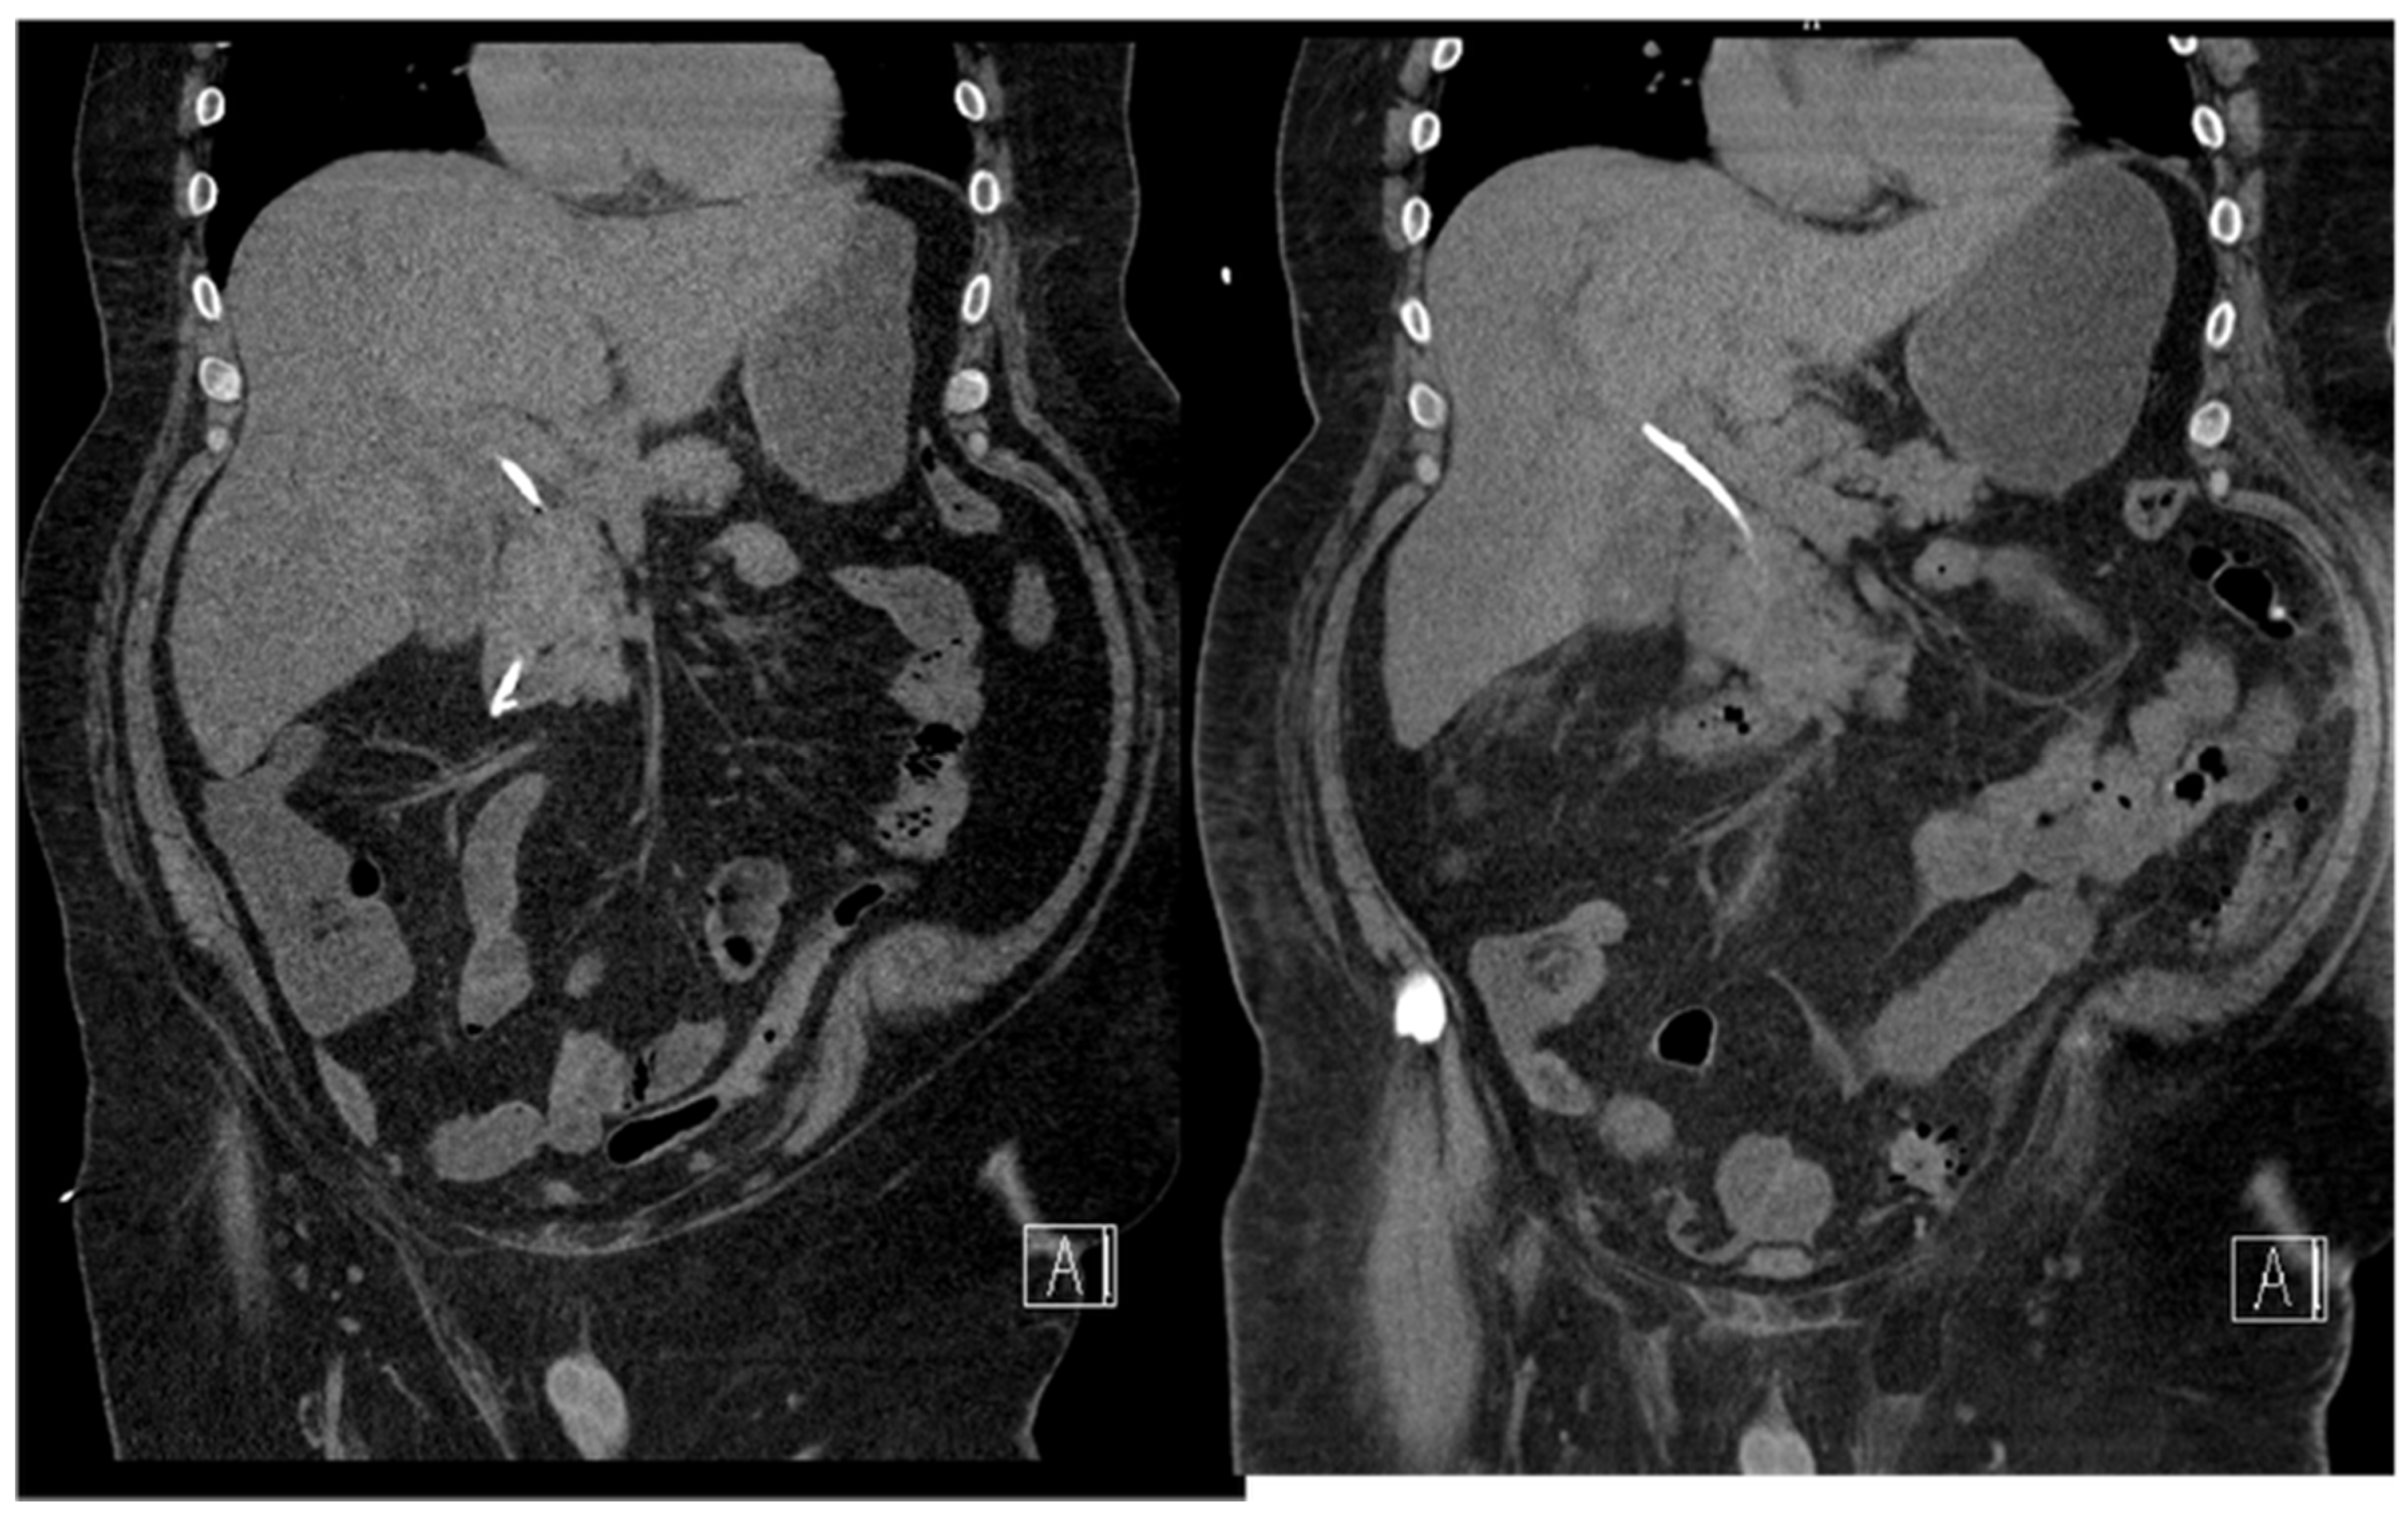

- 18.02: Contrast-enhanced CT demonstrated only mild hilar bile duct dilation, with no mass or lymphadenopathy (Figure 3).

- CT at readmission: No significant interval change, plastc stent in itu, no evidence of ductal dilation or masses (Figure 4).